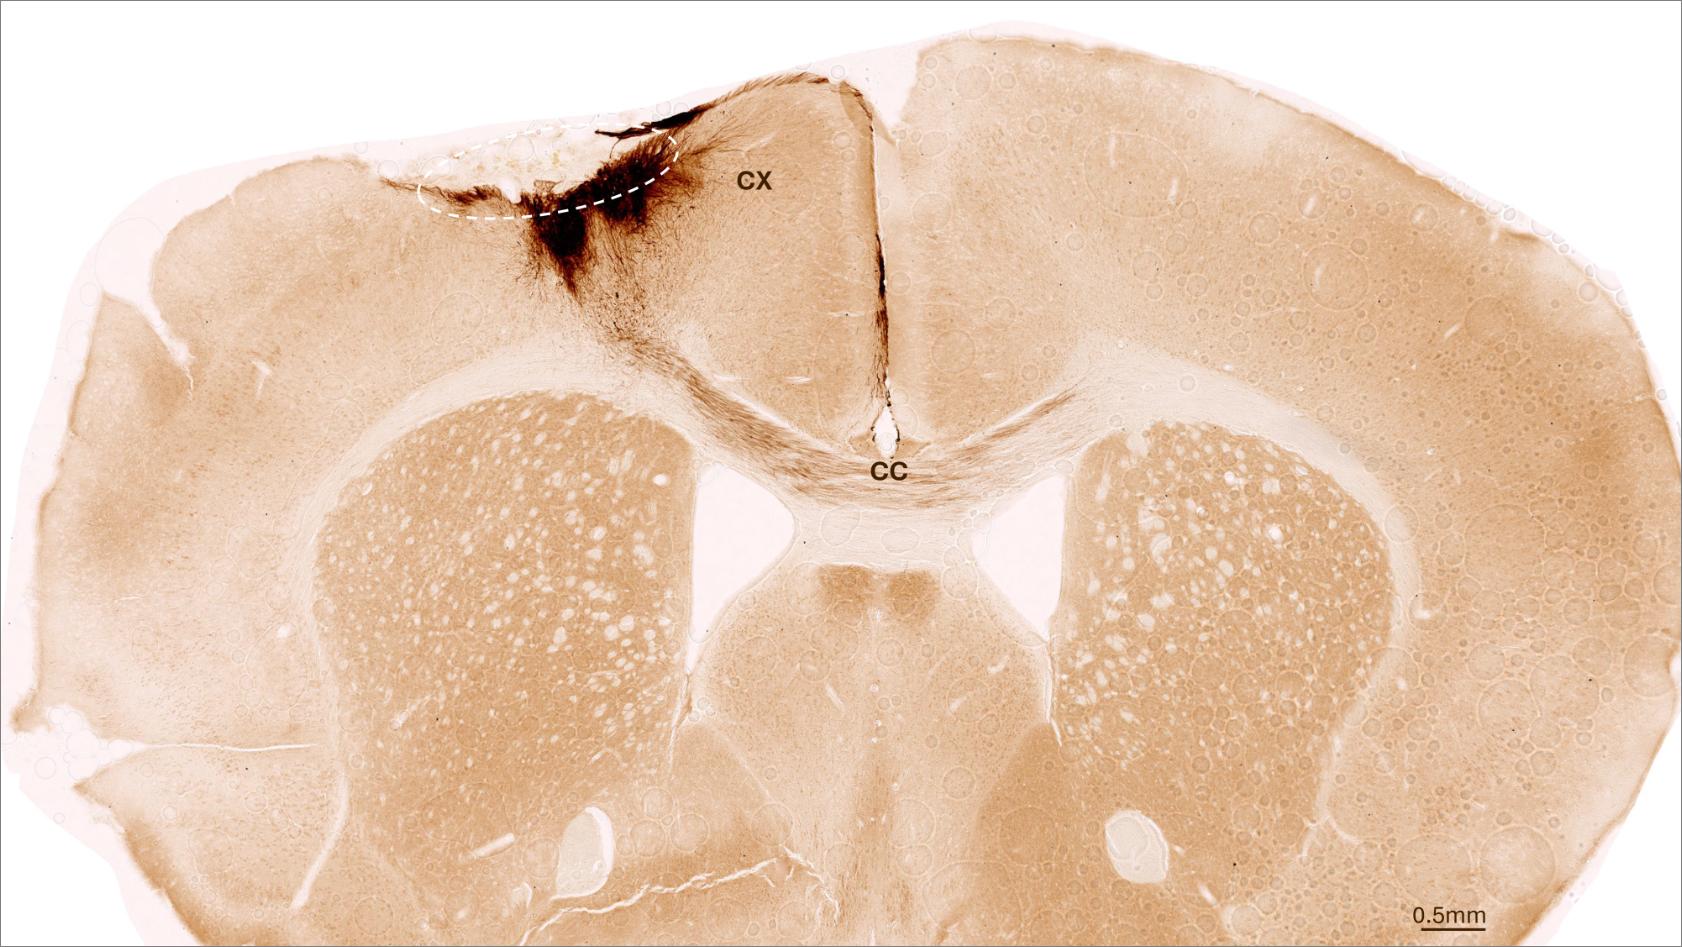

Hirnschnitt

Das Bild zeigt einen koronalen Schnitt durch das Gehirn einer Maus nach einem Schlaganfall und der Transplantation neuronaler Stammzellen. Die gestrichelte Linie markiert den Bereich des Schlaganfalls. Die Axone der transplantierten Zellen sind dunkelbraun gefärbt. Sie erstrecken sich lokal in den Kortex (CX), aber auch über den Balken (Corpus callosum, CC) in die gegenüberliegende Gehirnhälfte. (Bild: UZH)